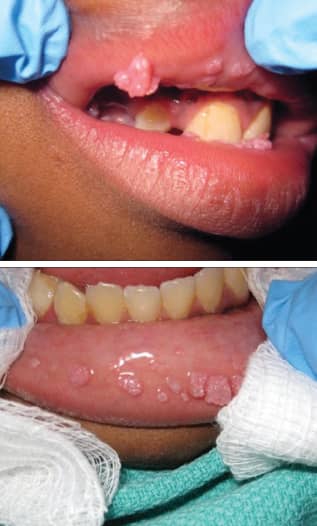

تصویر و شکل ظاهری زگیل تناسلی در دهان

زگیلهای دهانی در تصویر و معاینه بالینی ظاهری متفاوت دارند. برای شناخت بهتر این ضایعات، توصیف دقیق ویژگیهای ظاهری آنها ضروری است:

- رنگ: معمولاً همرنگ پوست، سفید، صورتی یا خاکستری است.

- شکل: ممکن است به شکل برجستگیهای کوچک و منفرد، خوشهای شبیه گل کلم، یا ضایعات مسطح دیده شوند.

- بافت: نرم، مرطوب و گاهی زبر.

- اندازه: از چند میلیمتر تا چند سانتیمتر متفاوت است.

- محل: روی زبان، داخل لبها، لثه، کام، لوزهها و ته حلق.

در بسیاری از موارد این زگیلها بدون علامت هستند و فرد مدتها بدون اینکه بداند ناقل ویروس است. به همین دلیل توجه به تصویر و ظاهر ضایعه اهمیت زیادی دارد، هرچند تشخیص قطعی حتماً باید توسط پزشک انجام شود.